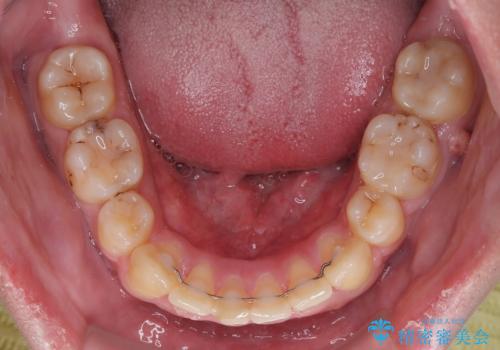

デコボコと口元の突出感を改善 抜歯矯正治療

患者様には辛抱強く治療にお付き合いいただき、すっきりとした口元に仕上げることができました。